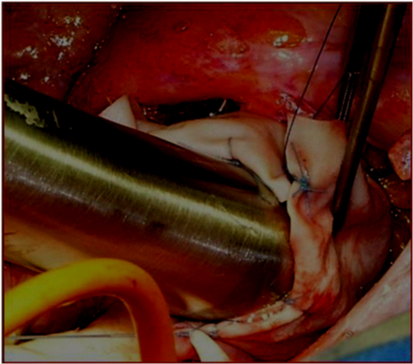

1. Remodeling of the valsalva sinuses: Mean diameter of the sinuses in our series was 52, 4mm. In the largest number of patients the only dilatation of the non-coronary sinus is present, that is why reduction of the non coronary sinus by resection or plication is enough in most cases (Figure 2).

Figure 2 Resection of the non coronary sinus.

2. Reduction of STJ: In all cases, sinotubular junction was dilated and the mean diameter was 43, 3mm, causing different grade of aortic insufficiency. Plication of the sinotubular junction must be done after measuring the diameter of the aortic annulus. The size of sinotubular junction after the plication must be 15-20% less than the aortic annulus diameter (Figure 3 & 4)

Figure 3 Plication of the sinotubular junction.

Figure 4 The size of sinotubular junction after the plication must be 15-20% less than the aortic annulus diameter.